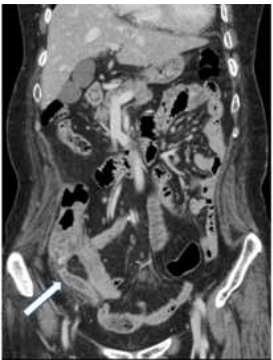

72.病人主訴右下腹逐漸悶痛、腹脹、反胃一整天。腹部電腦斷層檢查呈現如附圖。箭號所指之異常最符合下列 那一項初診斷? (A)cecal diverticulitis (B)acute appendicitis (C)mesenteric adenitis (D)colon cancer